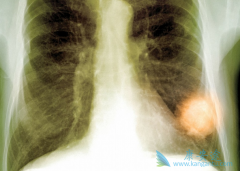

泰瑞莎 (AZD9291)在国内获批有一段时间了,这个肺癌靶向药一直以来备受患者的关注,不论是一线还是三线,均能使患者获得好的收益。而PD-1药物也是近两年比较火的抗癌药物,在肺癌治疗上有显着的疗效,那泰瑞莎和PD-1药物能否强强联手呢?它的效果是增 ...